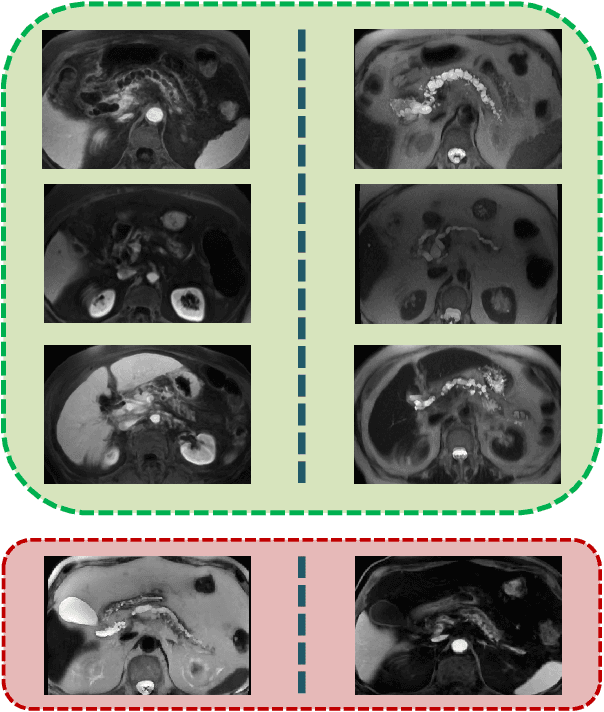

Abstract:Automated volumetric segmentation of the pancreas on cross-sectional imaging is needed for diagnosis and follow-up of pancreatic diseases. While CT-based pancreatic segmentation is more established, MRI-based segmentation methods are understudied, largely due to a lack of publicly available datasets, benchmarking research efforts, and domain-specific deep learning methods. In this retrospective study, we collected a large dataset (767 scans from 499 participants) of T1-weighted (T1W) and T2-weighted (T2W) abdominal MRI series from five centers between March 2004 and November 2022. We also collected CT scans of 1,350 patients from publicly available sources for benchmarking purposes. We developed a new pancreas segmentation method, called PanSegNet, combining the strengths of nnUNet and a Transformer network with a new linear attention module enabling volumetric computation. We tested PanSegNet's accuracy in cross-modality (a total of 2,117 scans) and cross-center settings with Dice and Hausdorff distance (HD95) evaluation metrics. We used Cohen's kappa statistics for intra and inter-rater agreement evaluation and paired t-tests for volume and Dice comparisons, respectively. For segmentation accuracy, we achieved Dice coefficients of 88.3% (std: 7.2%, at case level) with CT, 85.0% (std: 7.9%) with T1W MRI, and 86.3% (std: 6.4%) with T2W MRI. There was a high correlation for pancreas volume prediction with R^2 of 0.91, 0.84, and 0.85 for CT, T1W, and T2W, respectively. We found moderate inter-observer (0.624 and 0.638 for T1W and T2W MRI, respectively) and high intra-observer agreement scores. All MRI data is made available at https://osf.io/kysnj/. Our source code is available at https://github.com/NUBagciLab/PaNSegNet.